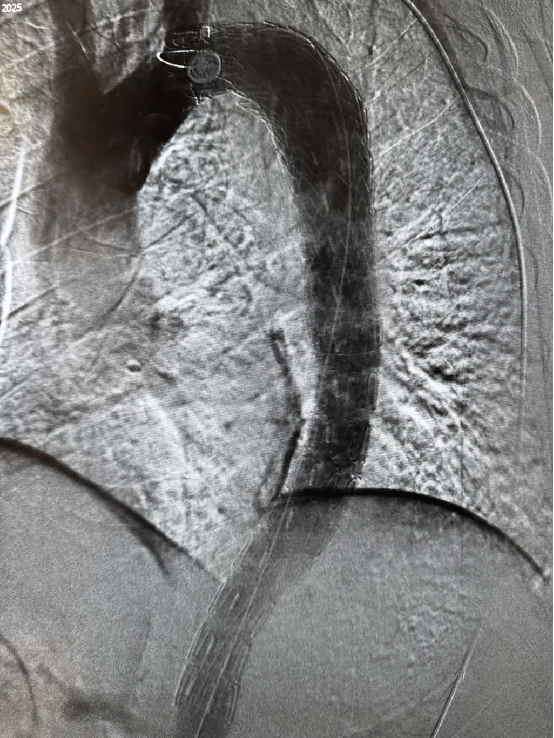

2025-11-0771岁老人主动脉夹层进急诊,血管介入科40分钟精准“拆弹”挽救生命

急诊铃响“心脏炸弹” 随时引爆“胸背像被刀割一样疼!” 11月5日,我院急诊科接入一名71岁男性患者,其血压飙升至 220/130mmHg,伴随大汗淋漓、濒死感。急诊科党妙杰医... -